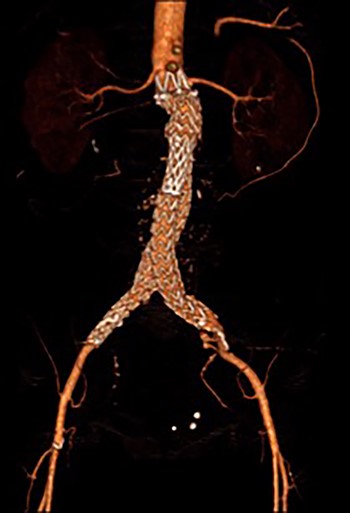

Post-EVAR angiogram showing acute thrombosis of the right limb and subtotal thrombosis of the left limb and trunk.

An angiogram at this stage demonstrated acute thrombosis of the right limb, and subtotal thrombosis of the left limb (Fig. 2). A further bolus of 2000 units Heparin was given intravenously. Thrombectomy was performed by advancing the 16Fr Sentrant sheaths into the limbs of the endograft followed by retraction under negative pressure. This manoeuvre restored antegrade arterial flow on both sides although there was a large volume of acute thrombus within the limbs of the endograft. A decision was made to perform intra-arterial thrombolysis. The 16Fr Sentrant sheath was removed from the left common femoral artery and haemostasis secured with the Proglides. The right-sided 16Fr sheath was downsized to 8 Fr sheath (the Proglide sutures were tightened around this sheath, achieving haemostasis around the smaller sheath). A multi-side hole straight angiographic catheter was placed in the body of the endograft for the thrombolysis. A bolus of 5 mg Actilyse (Boehringer Ingelheim, Ingelheim am Rhein, Germany) was given through this followed by a 1 mg/h infusion. An IV heparin infusion was started at 1000 units/h through the side arm of the 8 Fr sheath.